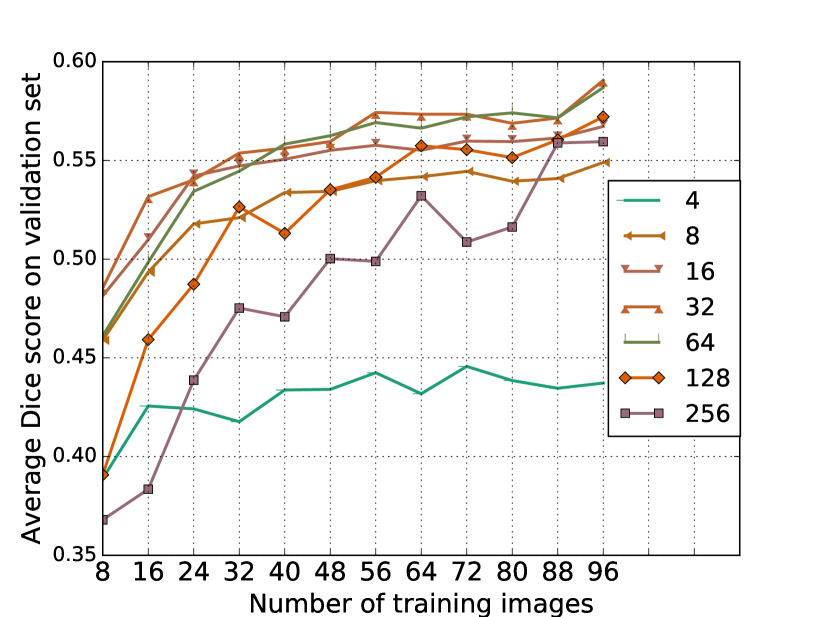

Tuning of GNN model is performed in three stages: hyperparameter tuning, pre-training and final model training. Using the dice loss in (3) for tuning, we set the number of GNN layers to and number of hidden units per layer to (see Figure 1(a)). We use Adam optimiser with learning rate and batch size of for training the GNN model. Further, we use all scans with automatic reference segmentations to pre-train the GNN model. For the comparing mean-field network model, we use the hyperparameter setting reported in [1].

The error measures in Table 1 indicate that as a stand-alone method, GNN model does not compare favourably to MFN model. For the combined case of GNN+MFN we see that there is reduction in the measure indicating that the GNN model is able to add missing branches that are not detected by the MFN model. There are two main reasons, we believe, for the observed performance of GNN model. Firstly, a limited amount of labelled data, which is reflected in Figure 1(a), wherein it appears that improvement in accuracy may follow from further increases in training set size. Secondly, the investigated GNN model models only nodes and does not take pairwise node interactions into account. For airway extraction tasks, modelling pairwise interactions can be beneficial [1]. A variation of GNN which explicitly learns representations for pairs of connected nodes may improve performance.